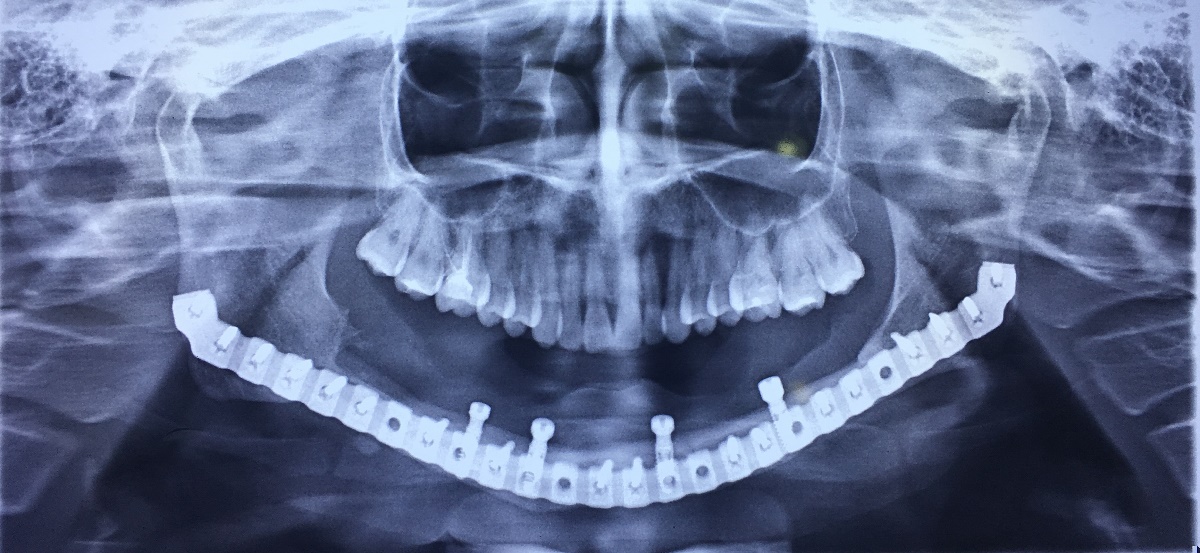

X-Quang trước điều trị

X-Quang sau cắt đoạn xương hàm dưới

X-Quang sau ghép xương mác

X-Quang sau cấy ghép răng (Implant)

X-Quang sau đặt phục hình tái tạo